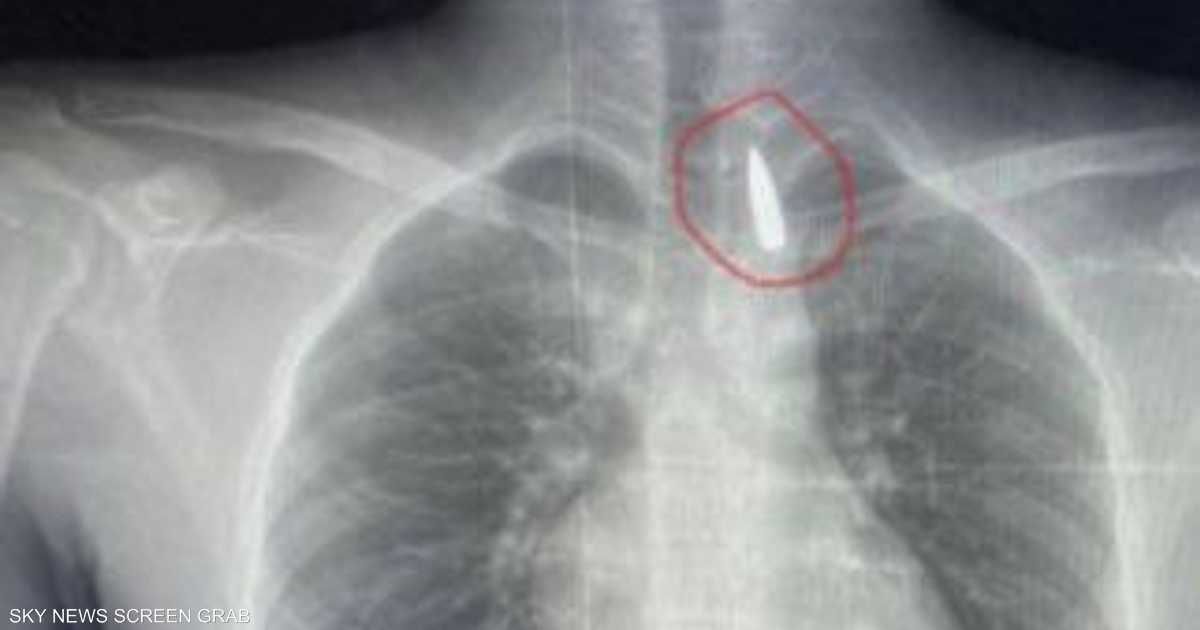

وأوضح عميد كلية الطب جامعة الإسكندرية ورئيس مجلس إدارة المستشفيات الجامعية تامر عبد الله، أن فريق من أطباء قسم جراحة القلب والصدر والتخدير والمعاونين تكمنوا من إجراء جراحة دقيقة بالغة الخطورة لأحد المرضى من قطاع غزة، والذي كان قد تعرض لإصابة بطلق ناري منذ فترة، استقر المقذوف على إثرها داخل تجويف القفص الصدري قرب الشريان الأورطي.

مبينا أن الفريق الطبي نجح، رغم دقة الحالة وتعقيدها، في استخراج المقذوف بأمان بعد عملية جراحية استمرت عدة ساعات داخل المستشفى الجامعي الجديد، حيث خضع المريض بعدها للرعاية الطبية اللازمة، مؤكدا أن حالة المريض حاليا مستقرة وتحت المتابعة الدقيقة من الفريق المختص.